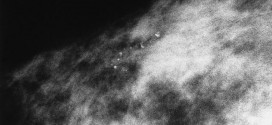

La hiperplasia maligna epitelial atípica de mama. Durante los primeros años de vida de una persona, las células normales se dividen más rápidamente para permitir el crecimiento. El cuerpo está compuesto por billones de células vivas. Las células normales del cuerpo crecen, se dividen formando nuevas células y mueren de manera ordenada. Una vez que se llega a la edad …